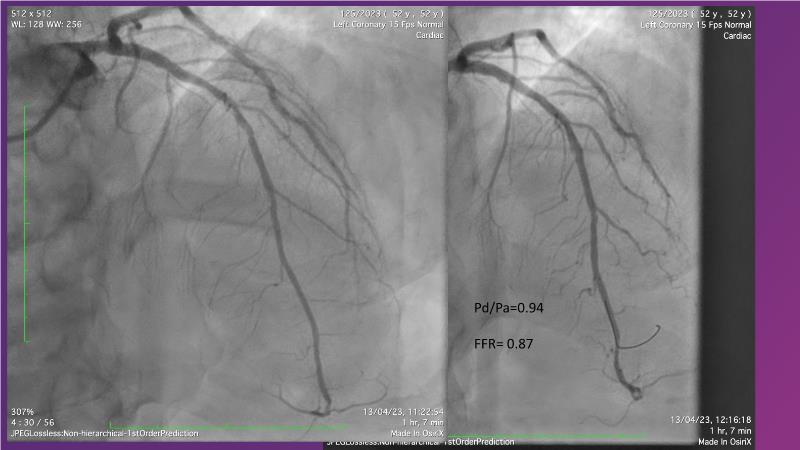

Follow this session to discover how accurate resting index can inform decision-making for DCB in CTO patients and understand the role of physiology in a new PCI workflow for complex MVD. Thus, you will learn about a DCB intention-to-treat strategy guided by post-PCI coronary physiology in complex lesions, review new procedural techniques and workflows from real-world cases, and explore the pros and cons of this novel approach.

- To learn about DCB intention-to-treat strategy guided by post-PCI coronary physiology in complex lesions

- To review new procedural technique and workflow from real world patient cases